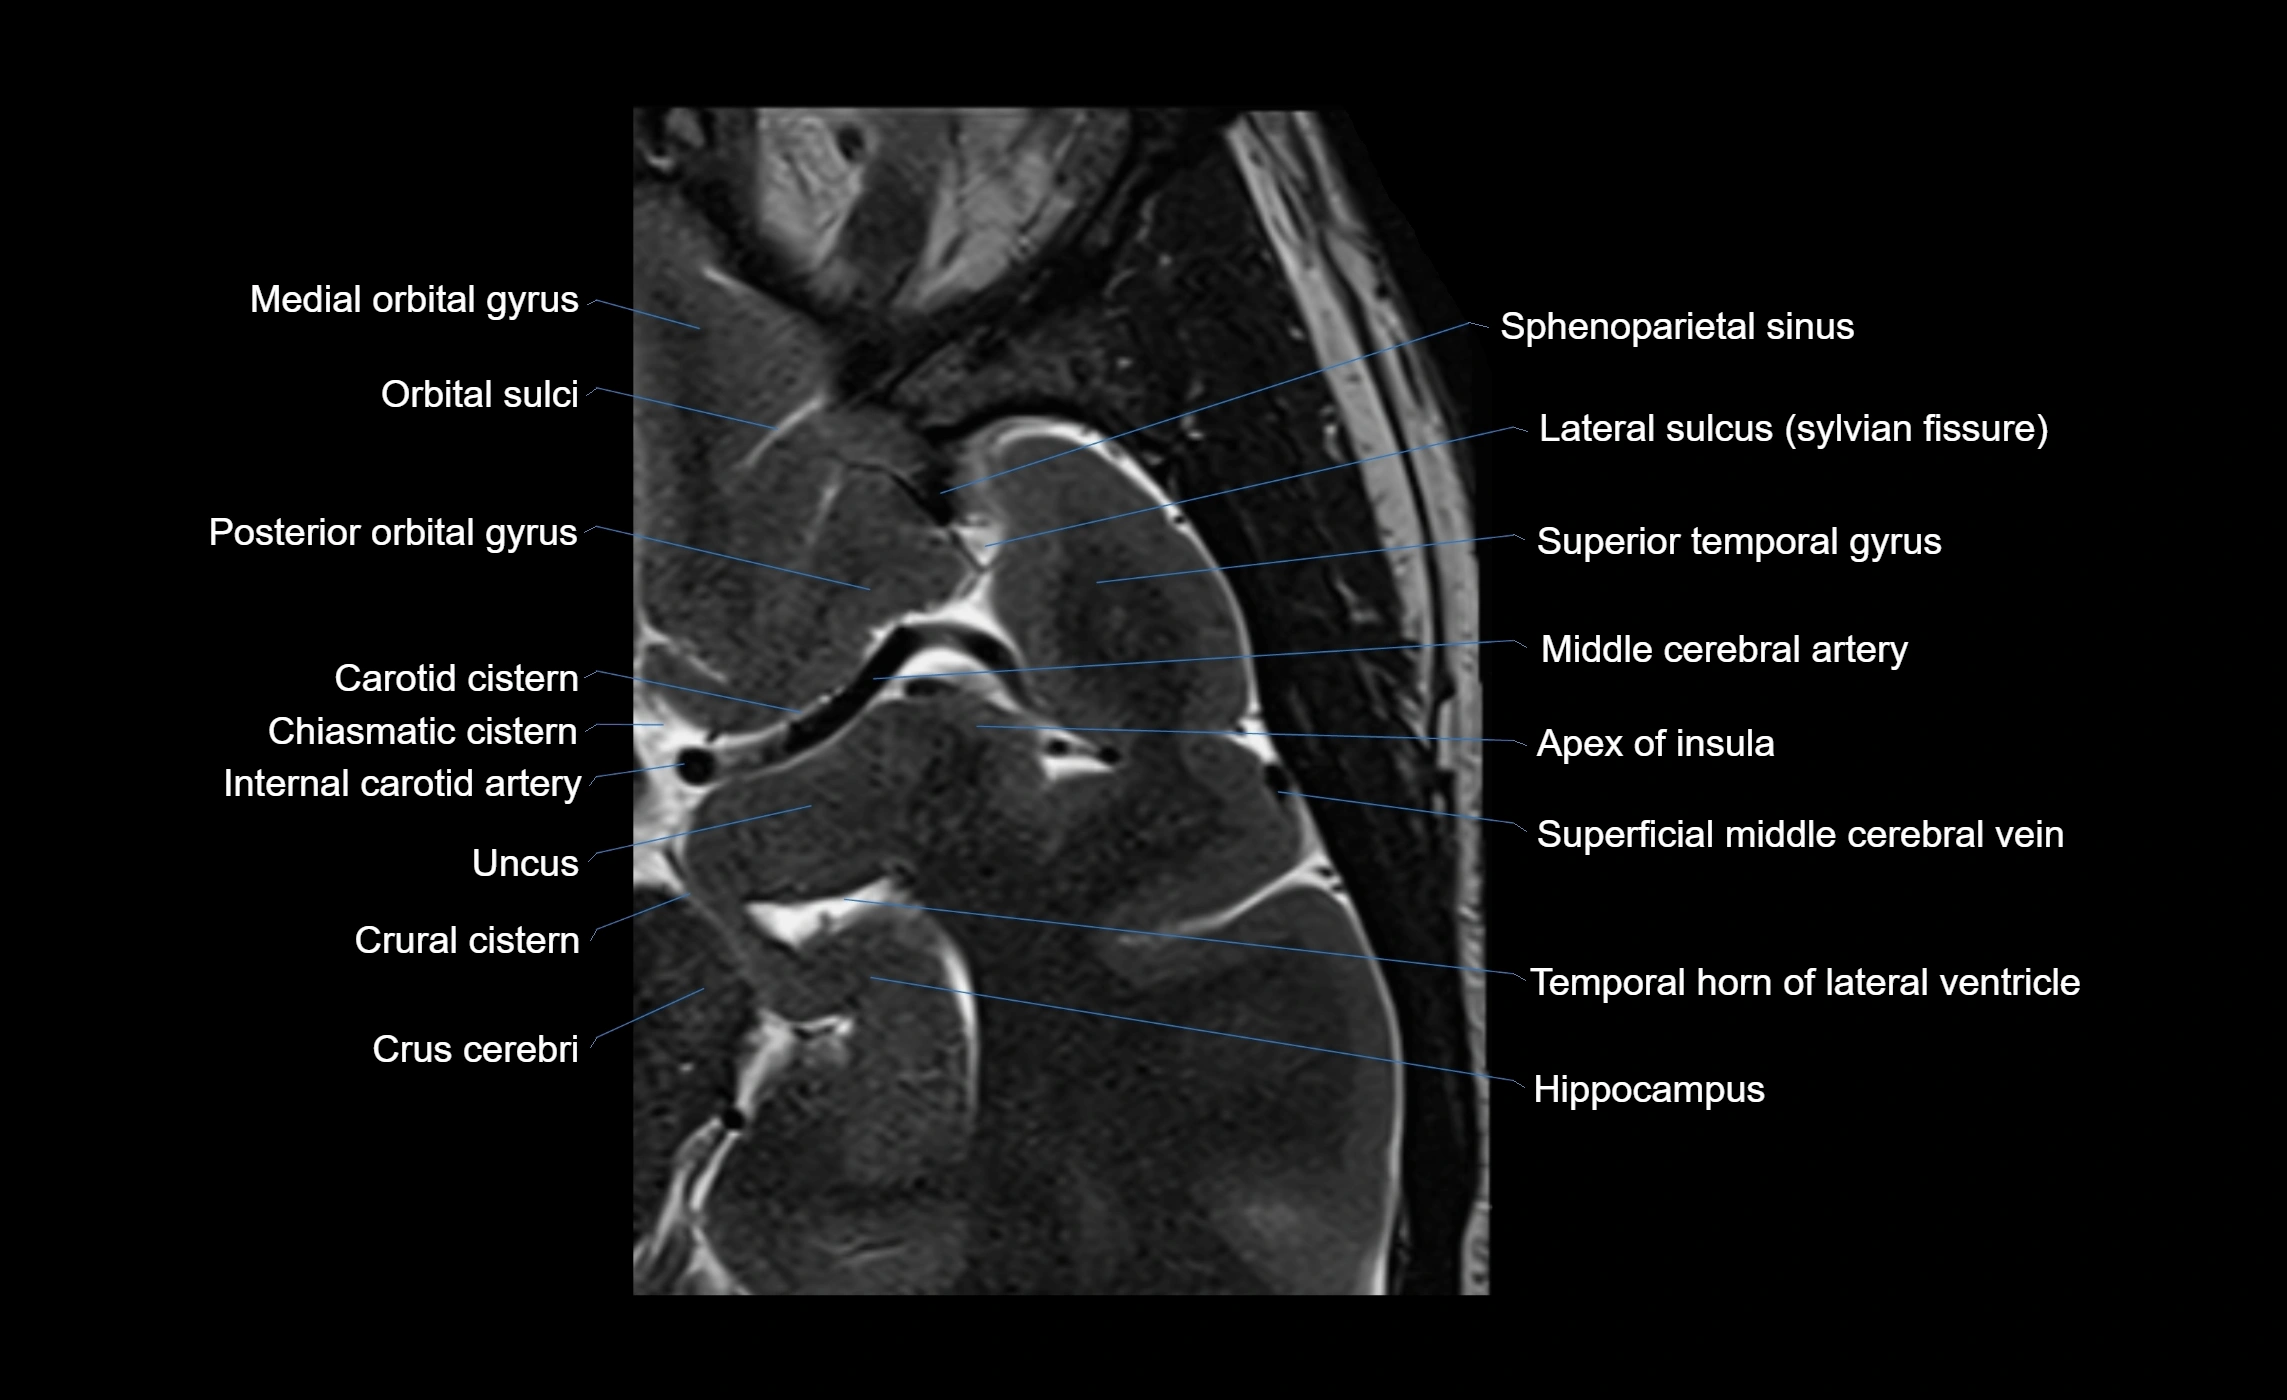

The anterior ascending ramus of the Sylvian fissure is a significant anatomical landmark in the lateral surface of the cerebral hemisphere. It represents one of the key branches of the Sylvian fissure (also known as the lateral sulcus) and plays an essential role in demarcating the boundaries between important cortical regions, notably within the frontal and parietal lobes. Understanding its anatomy and imaging appearance is crucial in neuroradiology, neurosurgery, and neuroanatomy for accurate localization and identification of adjacent brain structures.

• The anterior ascending ramus is a short, superiorly oriented branch that arises from the main stem of the Sylvian fissure.

• It projects upward (anteriorly and slightly dorsally) from the lateral sulcus into the inferior frontal gyrus.

• This ramus separates the pars opercularis (opercular part) from the pars triangularis (triangular part) of the inferior frontal gyrus.

• The anterior ascending ramus marks the boundary between Broca's area and adjacent cortical areas in the dominant hemisphere.

• Supplied predominantly by branches of the middle cerebral artery (MCA), particularly its opercular branches.

• The MCA runs within the Sylvian fissure and provides small cortical branches to adjacent gyri and sulci.

• Drained by superficial Sylvian veins (also called superficial middle cerebral veins), which follow the course of the Sylvian fissure.

• Venous blood ultimately drains into the sphenoparietal sinus and cavernous sinus.

MRI Appearance

• T1-weighted imaging:

• The Sylvian fissure and its anterior ascending ramus appear as low-signal intensity (dark) CSF-filled clefts between the gyri.

• Clear demarcation between adjacent gray and white matter.

• T2-weighted imaging:

• The fissure, including the anterior ascending ramus, is hyperintense (bright) due to CSF signal.

• Better visualization of the separation between opercular and triangular parts of the inferior frontal gyrus.